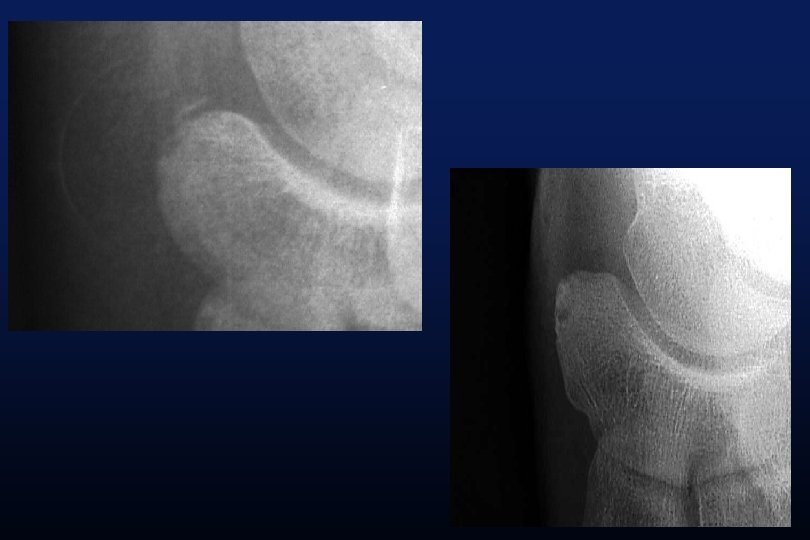

LES SYNOSTOSES DE L ’ARRIERE PIED Coalitions Tarsiennes (Tarsal Coalitions)

CALCANEO NAVICULAIRES (60%) TALO CALCANEENNES Synostoses et coalitions tarsiennes chez l'enfant. Étude de 68 cas chez 47 patients Ph. Rouvreau, J. C. Pouliquen, J. Langlais, C. Glorion, G. de Cerqueira Daltro The Too-Long Anterior Process Calcaneus: A Report of 39 Cases in 25 Children and Adolescents Pouliquen, J. C. M. D. ; Duranthon, L. D. M. D. ; Glorion, Ch. M. D. ; Kassis, B. Journal of Pediatric Orthopaedics Volume 18(3) June 1998 333 -336

Comfort 1998 Résection Coalition / surface sous talienne > 1/3 75% de mauvais résultats < 1/3 77% de bons résultats.